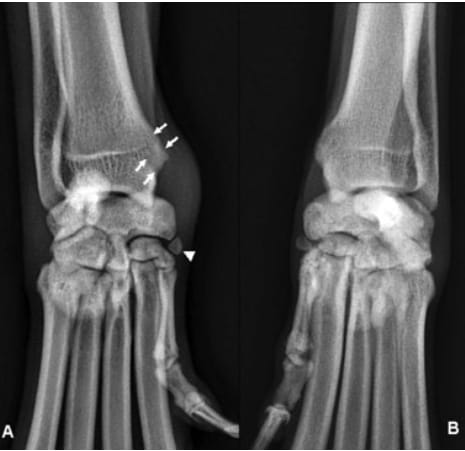

Fig. 2. Comparative radiographs of the carpus, 8-year-old male GoldenRetriever, agility training. (A) Right carpus, dorsopalmar view. The distalradial groove is radiolucent with radiopaque contours (arrows). Soft tissueswelling is present medial to the carpus. The sesamoid bone at the abductorpollicis longus insertion is visible (arrowhead). (B) Left carpus, dorsopalmarview. Normal distal radius and carpus.